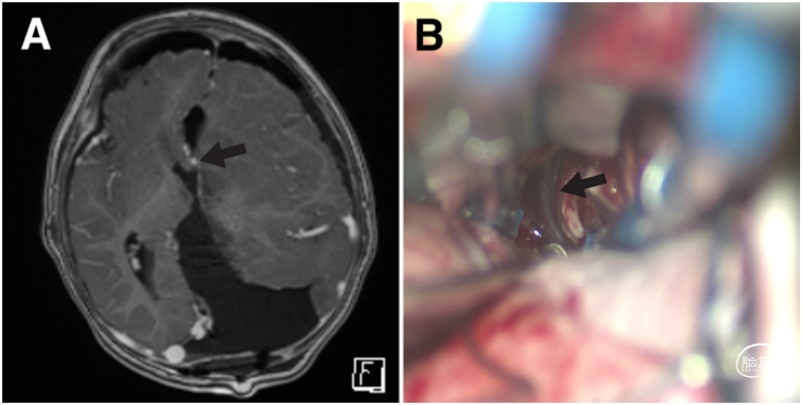

图5. A.术后MRI-T1加权增强轴位成像显示,胼胝体切开后的三脑室静脉(箭头)。B.术中照片示,胼胝体切开后显露的静脉(箭头)。